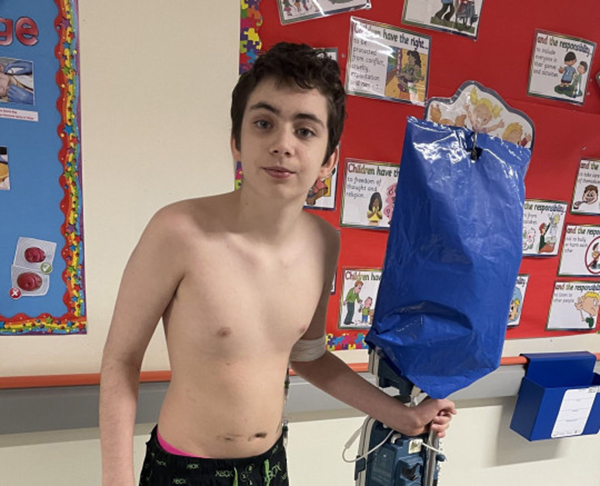

இங்கிலாந்து நாட்டில் உள்ள ப்ரீஸ்ட்விச் பகுதியை சேர்ந்தவர் 12 வயதான ரிலே மோரிசன். இவருக்கு, அறிவியல் ஆ.ரா.ய்.ச்.சி.க.ள் கு.றி.த்.த ப.ரிசோ.த.னையில் ஈ.டுப.டுவதில் மிகவும் ஆ.ர்.வ.மு.டை.ய.வ.ர். அந்த வகையில் ரிலே மோரிசன் சமீபத்தில் வி.பரீ.த ப.ரிசோ.தனை ஒன்றை மேற்கொள்ள மு.ய.ற்ச்சி செ.ய்து.ள்ளார்.

இதனை தொடர்ந்து, சுமார் 6 மணி நேர அ.று.வை சி.கி.ச்.சை.க்கு பிறகு மருத்துவர்கள் சிறுவனின் உ.டலில் இ.ருந்த 54 காந்த கு.ண்.டு.களை வெ.ளியே எடுத்துள்ளனர். தற்போது சிறுவன் மருத்துவமனையில் தொடர்ந்து சி.கி.ச்.சை பெற்றுவருவதாகவும், அவர் நலமுடன் இருப்பதாகவும் மருத்துவர்கள் தெ.ரி.வி.த்து.ள்ளனர்.